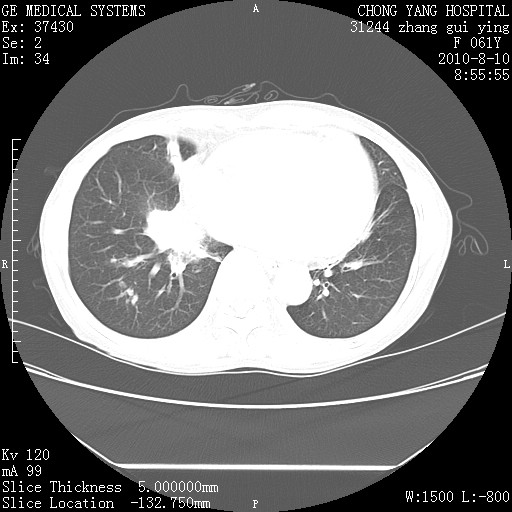

标题: CT28314:F61Y胸部增强,发热咳嗽一周入院,后面的为一周前平 [打印本页]

标题: CT28314:F61Y胸部增强,发热咳嗽一周入院,后面的为一周前平

右肺下叶中心性肺癌可能性大

1、支持考虑右侧中央型肺癌伴右肺中叶节段性不张及下叶支气管黏液痰栓    2、左肺上叶舌段感染。

支持右下肺中央型肺癌并左上肺感染.

我也觉得右肺中叶支气管受累

双肺感染性病变,不除外合并结核感染。

确切的说:1:右肺下叶中心型肺癌侵及中叶支气管并中叶不张,纵膈淋巴结转移。2:左肺舌叶炎症。3:右侧胸腔少量积液

1:右肺下叶中心型肺癌侵及中叶支气管并中叶不张,纵膈淋巴结转移。2:左肺舌叶炎症。3:右侧胸腔少量积液。支持!

右肺下叶内基底段近膈不规则肿块,考虑右肺下叶周围型肺癌可能性大。